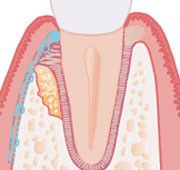

2. Guided Tissue Regeneration

What is Guided Tissue Regeneration?

A more recently developed type of regenerative surgery depends on guiding the proper tissue to heal the periodontal lesions. Gum tissue heals very quickly, and after surgery migrates down into the bone pocket quickly. Unfortunately, this does not allow time for the bone to refill the pocket, so the defect persists. With guided tissue regeneration, the gum tissue is excluded from the bone defect with a resorbable membrane, allowing time for the bone to fill back in. This technique has been available for 18 years, and in certain areas is extremely predictable.

Defect

Membrane isolating defect so bone has time to heal

New bone forming as membrane dissolves